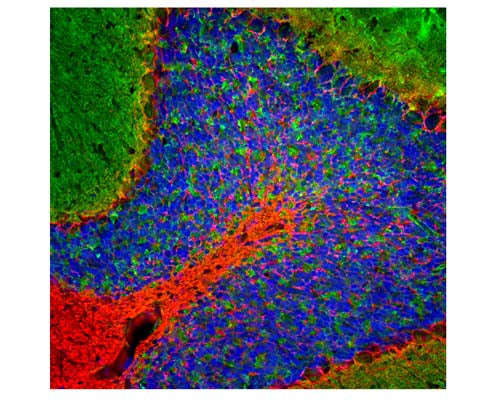

Image of a rat cerebellum section by Immunofluorescence and Immunohistochemistry. The section was stained with R-2113-50, Neurofilament light polypeptide, C-terminus, (NF-L-Ct), Rabbit pAb, (red, 1:5,000), and co-stained with product M-2106-100, Beta-Synuclein, Clone 6A10, Mouse mAb, (green, 1:5,000), and Hoechst staining of nuclear DNA (blue). Method: Following transcardial perfusion of rat with 4% paraformaldehyde brain was fixed for 24 hours, cut to 45 uM, and free-floating sections were stained with antibodies. Product R-2113-50 labels dendrites and axons of the neuronal cells whilst product M-2106-100 detects protein that is concentrated in the synaptic regions.

Click on image to zoom